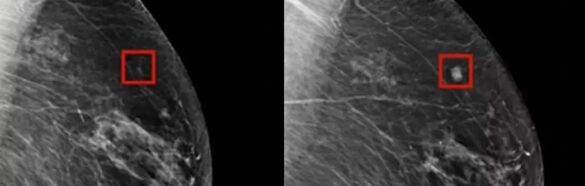

Nová technológia používajúca AI však umožňuje detekovať rakovinu prsníka oveľa skôr, než by to dokázali lekári. Podľa nedávneho článku v CNN, AI program bol schopný úspešne zistiť rakovinu prsníka u ženy až štyri roky predtým, než sa vyvinula a bola diagnostikovaná tradičnými metódami.

Tak ako to funguje? AI sa používa na skríning rakoviny prsníka s cieľom identifikovať potenciálne problémy ešte dlho predtým, než sa vyvinú do niečoho škodlivého. Technológia funguje tak, že strojové učenie (machine learning) umožňuje AI vyhodnocovať obrazy a porovnávať ich s tými, ktoré už boli zaznamenané v stroji, aby identifikovali nezrovnalosti a prípadné rizikové oblasti.

Podľa Dr. Larryho Nortona z Lauder Breast Center, AI pomáha radiológom lepšie pozrieť sa na obrazy a identifikovať oblasti, ktoré by si možno inak nevšimli. Výhoda tejto technológie spočíva v tom, že dokáže identifikovať potenciálny rizikový faktor u pacienta ešte predtým, než sa vyvinie rakovina.